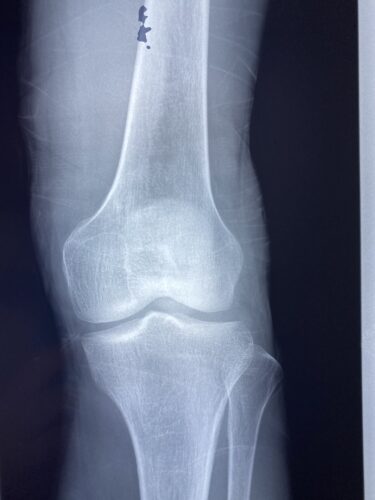

牛久市から来院された人工関節置換術後の痛みでお困りの症例(保険外対応)